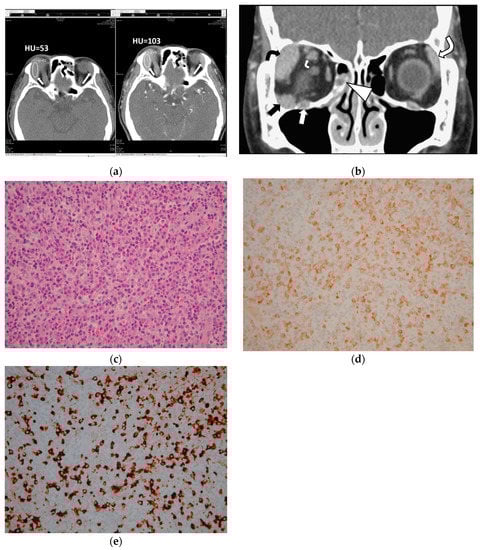

This study measured CTHU for all 47 orbital lesions of 25 patients on both pre and postcontrast prebiopsy CT scans. The region of interest (ROI) maker in an oval shape was placed in the center of each lesion to cover 50% of the largest tumor area on CT axial images, avoiding the inclusion of bone and blood vessels (Figure 1). This study also calculated postcontrast CTHU divided by precontrast CTHU.

A pathologist (AFYL) reviewed the pathologic sections of the 25 patients. The pathologic review concluded 13 patients with extranodal marginal zone lymphoma of mucosa-associated lymphoid tissue (MALT lymphoma), 1 with low-grade B cell lymphoma with plasmacytic differentiation, 1 with diffuse large B cell lymphoma, 1 with follicular lymphoma and 9 with IgG4-ROD. The histopathologic findings of the 9 patients with IgG4-ROD showed diffuse lymphoplasmacytic infiltration, IgG4-positive (IgG4+) plasma cells, IgG-positive (IgG+) plasma cells and various degree fibrosis. Seven (78%) of the nine IgG4-ROD patients showed IgG4+ cells > 100 cells/HPF and IgG4+/IgG+ ratio > 40% (Figure 1). Another 2 of the 9 IgG4-ROD patients (22%) had IgG4+ plasma cell < 50 cells/HPF and IgG4+/IgG+ ratio > 40%.

Specifically, of the 16 patients with OL, eleven (69%) had a solitary tumor in an orbital cavity or at eyelids, 1 (6%) had 2 tumors, 2 (13%) had 3 and 2 (13%) had 4. The other 9 out of the 25 patients had IgG4-ROD: 2 (22%) with 1 tumor; 5 (56%) with 2 tumors, 1 (11%) with 3 tumors and 1 (11%) with 5 tumors. CT features statistically significantly associated with IgG4-ROD included lesions with regular borders (p = 0.0069), multiple tumors (p = 0.0414), lacrimal gland involvement (p = 0.0085), lesions involving bilateral lacrimal glands and bilateral orbital cavities (p = 0.0022 and p = 0.0168, respectively, Figure 1).

In contrast, tumors involving the extraconal, conal or intraconal space, lacrimal sac, optic nerve, extraocular muscle tendon, infraorbital nerve, preseptal space and presence of sinusitis and bone remodeling were ineffectual to differentiate IgG4-ROD from orbital lymphoma (Figure 1 and Figure 2; all p > 0.05, Fisher’s exact test). Two IgG4-ROD patients and 6 OL patients had a solitary tumor involving the preseptal space (Figure 2).

Figure 1. A 68-year-old man with immunoglobulin G4 (IgG4)-related orbital disease (IgG4-ROD) shows multiple tumors in bilateral orbital cavities. (a) Axial computed tomography (CT) scans show masses in bilateral lacrimal glands (short and large arrows). The mean value of CT Hounsfield unit scale (CTHU) is measured at the enlarged right lacrimal gland (short arrows) on a picture archiving and communication system monitor. The region of interest (ROI) marker in an oval shape is placed in the center of the mass (short arrows) to cover 50% of the largest tumor area. The mean value of precontrast CTHU is 53 and that of postcontrast CTHU is 103. Sinusitis is found in the left frontal sinus with mucus retention (black curved arrows); (b) Coronal postcontrast CT scan shows multiple masses or enlargement in various ophthalmic tissues with regular borders and homogeneous contrast enhancement in bilateral orbital cavities as follows: a mass at the extraconal compartment of the right orbital cavity (black arrow),the right lacrimal gland (black curved arrow), the left lacrimal gland (large white curve arrow), the right superior rectus muscle belly (small white curve arrow) and the right infraorbital nerve (white arrow). Sinusitis is noted in the right ethmoid sinus with mucus retention (arrowhead); (c) Pathologic specimen shows infiltration of many lymphoplasma cells and mild fibrosis (hematoxylin–eosin stain, original magnification ×200); (d) Immunostaining for immunoglobulin G (IgG)-expression shows many plasma cells are positive for IgG stains (original magnification ×200); (e) Immunostaining for IgG4-expression shows abundant IgG4-positive plasma cells have infiltrated the lesion. IgG4-postive/IgG-positive plasma cell ratio is more than 40%. There are more than 100 IgG4-positive plasma cells in one high-powered field (>100/HPF) (original magnification ×200).